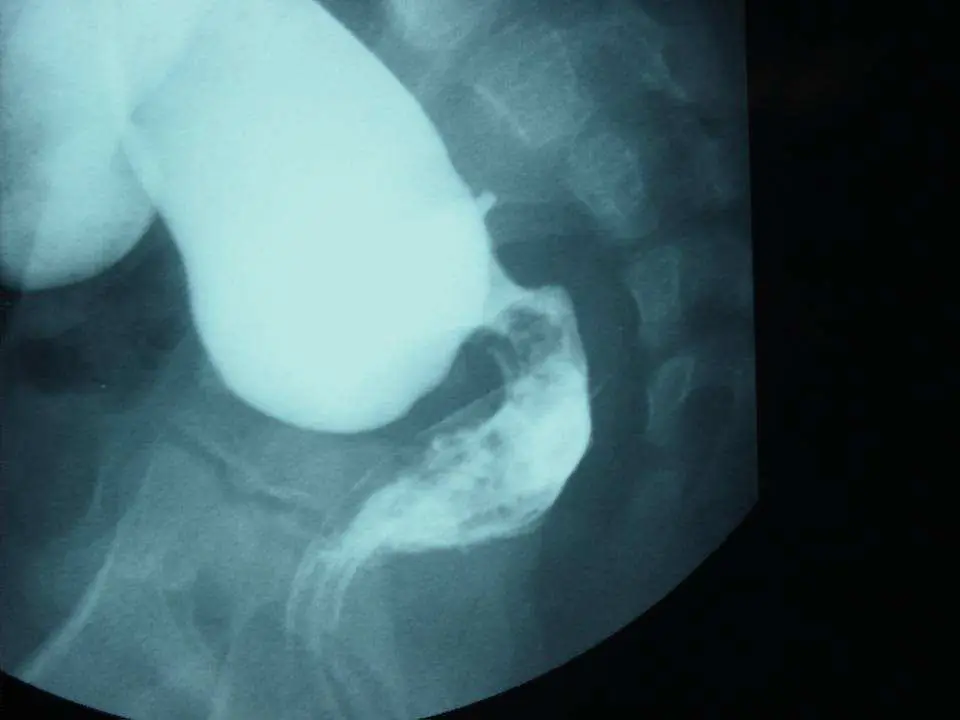

一個剛出生五天的嬰兒,有腹部腫脹( abdominal distention )和延遲性胎便排出( delayed meconium passage ),下消化鋇劑攝影顯示如下:此病人最可能的診斷為何?

本圖為新生兒下消化道鋇劑攝影(lower GI contrast study / barium enema),側位(lateral view)影像。

主要影像發現:

- 影像上可見明顯的移行區(transitional zone):近端腸道顯著擴張,充滿鋇劑呈現較大口徑的含鋇腸管;往遠端直腸方向可見管腔明顯縮窄

- 縮窄的遠端腸段(直腸/乙狀結腸遠端)呈相對細小口徑,為無神經節細胞區段

- 近端的擴張腸管與遠端狹窄段之間,呈典型漏斗狀(funnel-shaped)移行

- 骨盆腔骨骼(薦椎、髂骨)清晰可見,確認為側位骨盆攝影

影像學意義: 此移行區(transitional zone)是巨結腸症最重要的影像學診斷依據。正常嬰兒的直腸口徑應大於乙狀結腸(直腸作為糞便蓄積之用),Hirschsprung's disease 時因無神經節細胞段(aganglionic segment)無法正常舒張,導致直腸較乙狀結腸細小,稱為直腸乙狀結腸比值(rectosigmoid index)倒轉